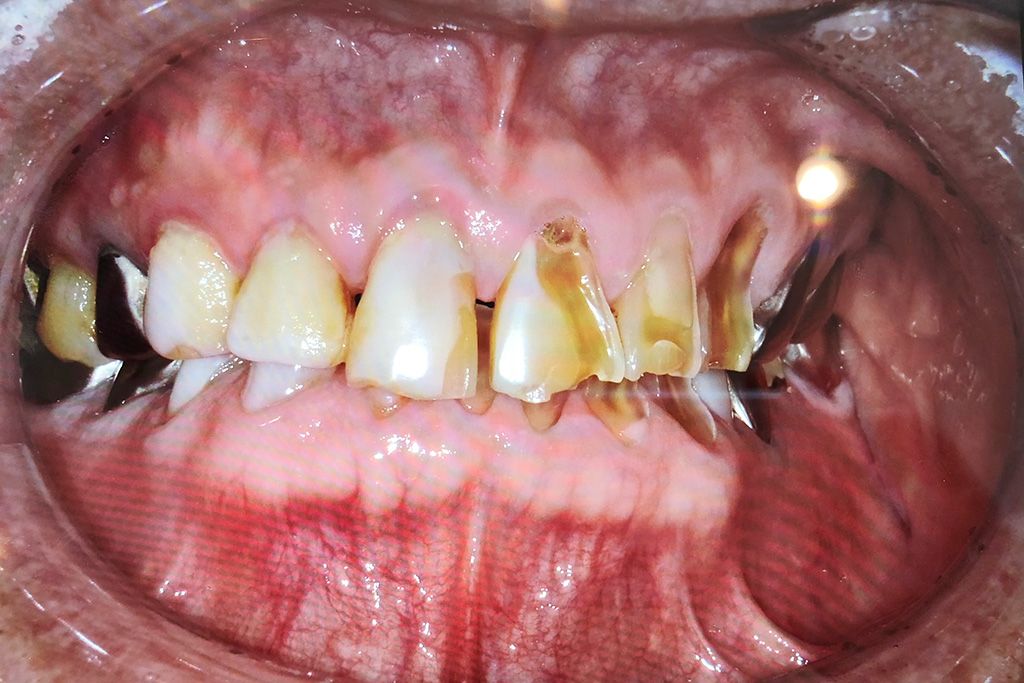

以前は、根尖病変などから

排膿している歯肉の開口部を

【フィステル(瘻孔)】と呼んでいました。

しかし現在は、

サイナストラクト(sinus tract)

という名称が使われることが増えています。

「フィステル」は本来、

を指す医学用語です。

一方、歯科で見られる多くの排膿路は、

そのため、より正確な用語として

【サイナストラクト(排膿路)】が

用いられるようになりました。

以前 | 現在 |

フィステル | サイナストラクト |

瘻孔(交通路) | 排膿路という意味合いが強い |

つまり、

より病態に即した正確な表現へと変わった

ということです。

臨床でも「フィステルですね」ではなく

「サイナストラクトが認められます」と

表現する流れになっています。